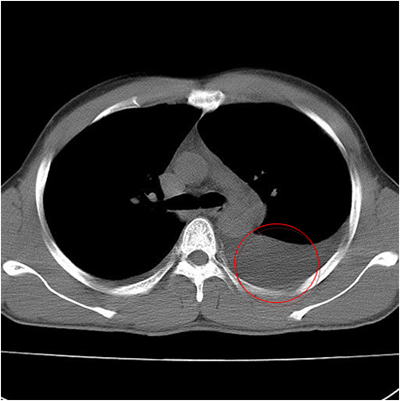

左侧胸腔积液的CT图像

在系统抗结核治疗基础上配合胸腔穿刺抽取胸腔积液是目前治疗结核性胸膜炎的常规治疗方法,但是部分患者胸腔积液吸收不良出现胸膜增厚、胸膜粘连、肺组织局部膨胀不全,从而导致肺功能受损、并且可伴有不同程度的胸痛,影响患者的预后生活质量和身体素质,尤其是对于青、中年这一主要的劳动力群体。据报道在所有结核性胸膜炎患者中,有20%-50%可发生2-10mm的残余胸膜增厚,并且在发病后5-7天即可形成,临床预后不良率可达15.2%,严重者可致胸廓变形塌陷、肺不张。